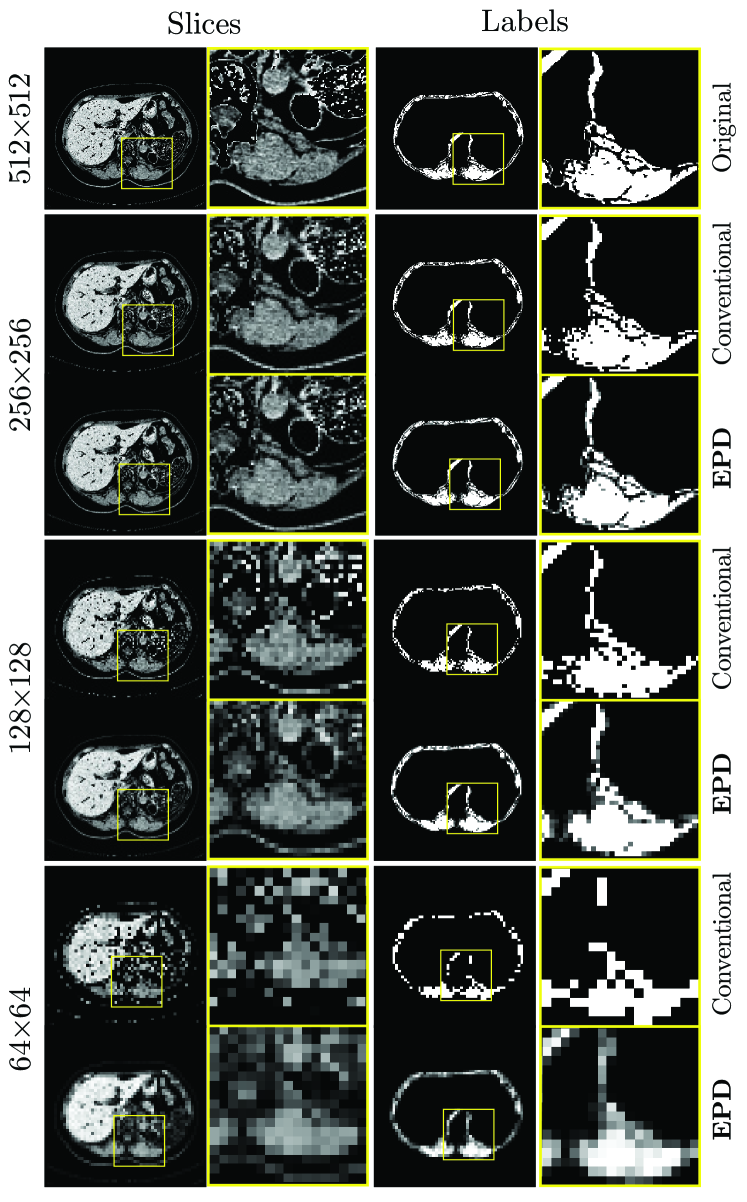

Refer to caption

Figure 3: Application of EPD to the high-resolution inputs of 512×512512512512\times 512. The conventional method employs bilinear and nearest-neighbor interpolation to downsample CT slices and labels, respectively. The window in yellow on the slices and labels is zoomed-in in the subsequent column.

Following [21], each CT slice is windowed to three different Hounsfield Unit (HU) ranges. These three channels, after downsampling, form a multi-channel input for the network. Similarly, the downsampled target labels are used for loss calculations. Fig. 3 illustrates the impact of downsampling on slices and labels. EPD transforms edges into floating-point probability values, which visually resemble anti-aliased edges. In contrast, nearest-neighbor interpolation disregards the presence of these pixels entirely, resulting in the loss of essential information, further leading to significant oversights in performance evaluation. When dealing with slices, averaging yields smoother edges while maintaining continuity better than bilinear interpolation.